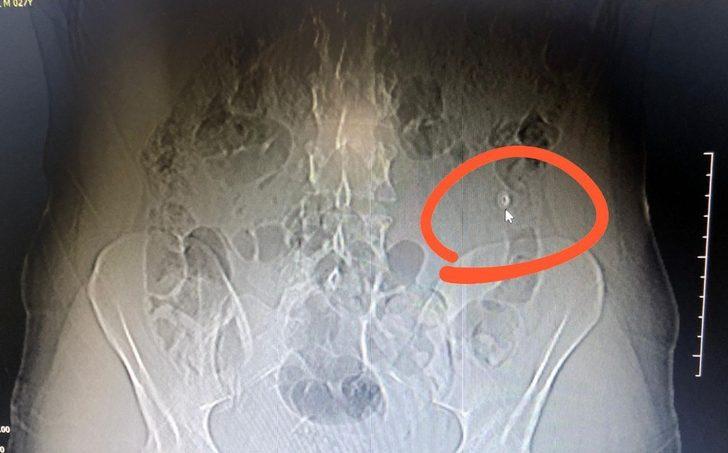

Marmaris Narkotik Grup Amirliği ekiplerinin uzun süredir takip ettiği uyuşturucu madde satıcısı Y.A. (27), polisleri görünce elinde bulunan uyuşturucu hapları ve maddeleri yuttu. Ekipler, Y.A.’yı hemen Marmaris Devlet Hastanesine götürdü. Hastanede çekilen tomografide zanlının midesinde yabancı maddeler olduğu ortaya çıktı. Yuttuğu haplardan etkilenen şahıs hastanede yapılan müdahalenin ardından emniyet merkezine götürüldü.